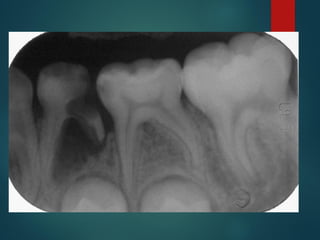

Clasificación

Radiográfica De las

Caries

 Incipiente de esmalte

 De esmalte

 Dentinaria superficial

 Dentinaria profunda

 Sobreproyectada en cámara pulpar

 Penetrante

Clasificación Radiográfica

De Las Caries